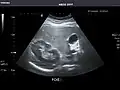

Abdominal ultrasound can be used to diagnose abnormalities in various internal organs, such as the kidneys,[1] liver, gallbladder, pancreas, spleen and abdominal aorta. If Doppler ultrasonography is added, the blood flow inside blood vessels can be evaluated as well (for example, to look for renal artery stenosis). It is commonly used to examine the uterus and fetus during pregnancy; this is called obstetric ultrasonography.[2][3]

Abdominal Ultrasound (Full Exam)

STRUCTURED REPORT

(Technique: Transabdominal ultrasonography; Device: Toshiba Aplio XG)

Liver: Diffusely homogeneous and normal in echogenicity. No focal mass or contour nodularity. No intrahepatic biliary ductal dilatation.

Portal Vein: Patent main portal vein.

Gallbladder: No stones, wall thickening, or pericholecystic fluid.

Common Bile Duct: Nondilated measuring 1.3 mm at the level of the porta hepatis.

Pancreas: Visualized portions unremarkable.

Spleen: Normal in size.

Kidneys: Right and left kidneys measure 11.5 cm and 12 cm in length respectively. No hydronephrosis. Small left lower pole kidney cyst.

Ascites: None.

Aorta: Visualized portions normal in caliber, 16 x 15 mm.

IVC: Normal.

IMPRESSION:

Normal abdominal ultrasound.